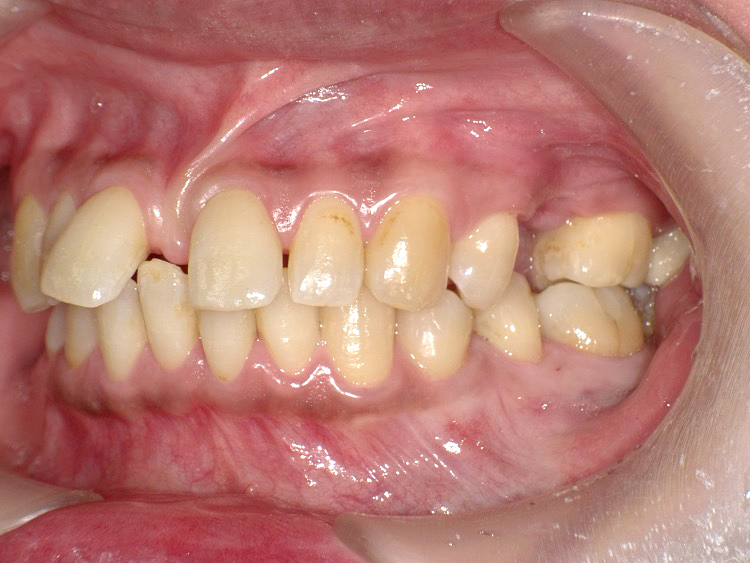

症例5

Before

After

| 主訴 | 上下3-3の並びが気になる |

|---|---|

| 年齢 | --- |

| 治療 期間 |

約1年 |

| 治療 内容 |

インビザライン5-5 |

| 治療費 | ¥517,000(税込)/調整料含む |

| 治療のリスク | 奥歯を動かさないので、前に出して並べていく。 歯と歯が移動するスペースを作るので、知覚過敏の症状がまれにでる。 歯を動かすことで、歯茎が下がるリスクある。 矯正終了後は、リテーナーを使用し、後戻りを防ぐ必要がある。 |